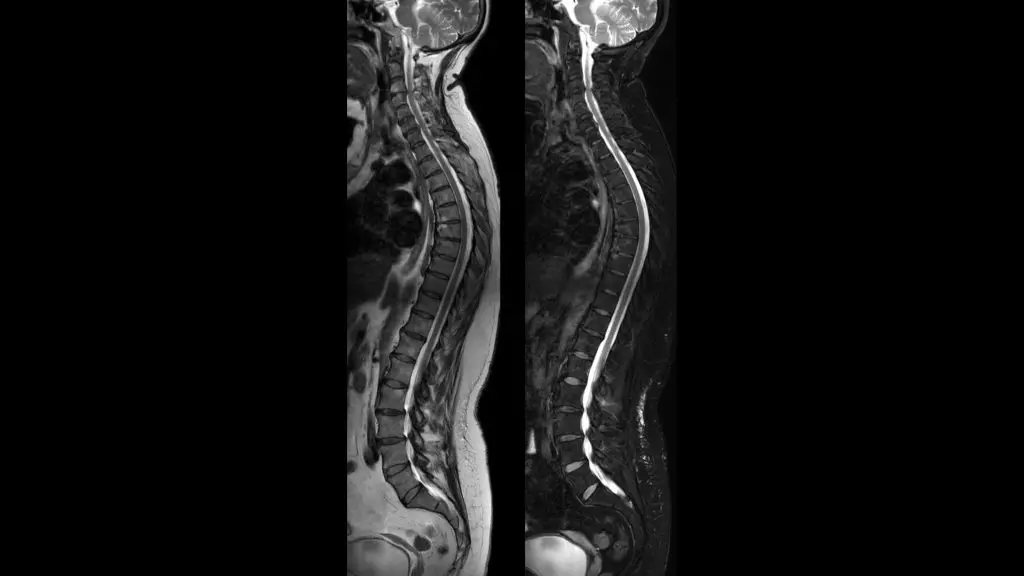

Heath Lodge Clinic are proud to announce that they have recently installed a new 3T MRI Scanner.

The Philips Ingenia Elition solution offers cutting-edge MR imaging techniques, while setting new standards for clinical research in 3.0T imaging based on gradient- and RF designs. The Ingenia Elition delivers on superb image quality, and performs MRI exams up to 50% faster¹. Fast overall exam-time is achieved by improving patient handling setup time at the bore with the touchless guided patient setup, combined with accelerations in both 2D- and 3D scanning. Furthermore, the Ingenia Elition offers an immersive audio-visual experience to calm patients and guide them through MR exams.